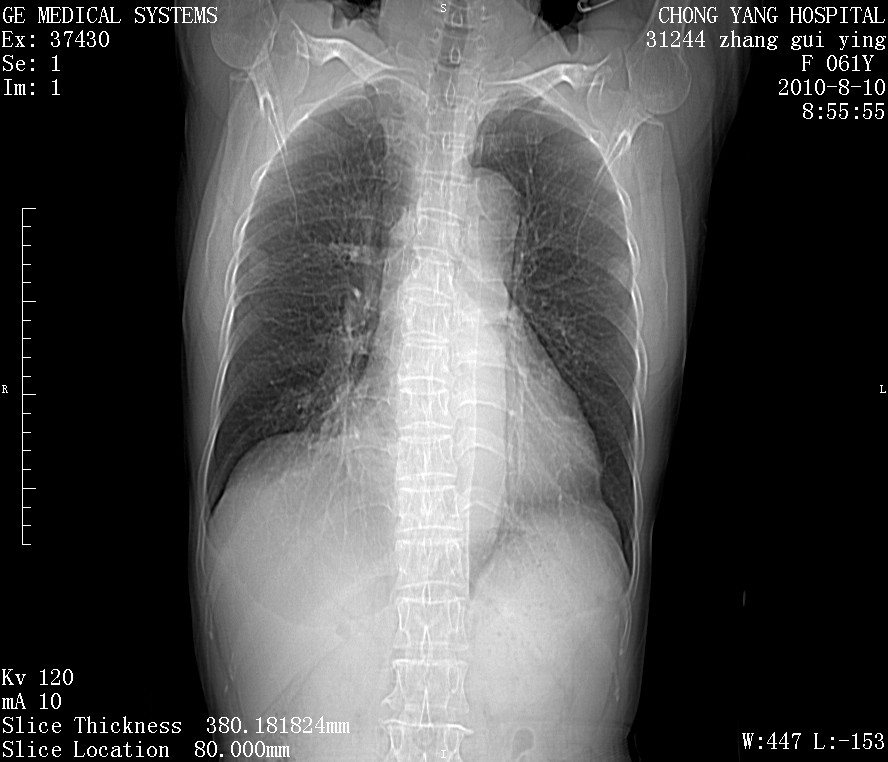

标题: CT28314:F61Y胸部增强,发热咳嗽一周入院,后面的为一周前平

右肺下叶中心性肺癌可能性大

1、支持考虑右侧中央型肺癌伴右肺中叶节段性不张及下叶支气管黏液痰栓    2、左肺上叶舌段感染。

支持右下肺中央型肺癌并左上肺感染.

支持3楼意见,还要考虑:纵隔及肺门淋巴结转移、右侧少量胸腔积液。

确切的说:1:右肺下叶中心型肺癌侵及中叶支气管并中叶不张,纵膈淋巴结转移。2:左肺舌叶炎症。3:右侧胸腔少量积液

块影平扫32hu,动静脉期62-70hu.

右肺下叶内基底段近膈不规则肿块,考虑右肺下叶周围型肺癌可能性大。

考虑右下肺肺癌,纵隔淋巴结转移i。